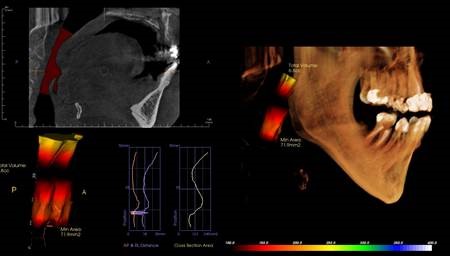

Airway health is very important to your health. Many people suffer from breathing disorders that relate to the airway, and many of these are sleep related. Someone with a small airway can have extreme difficulty moving air in and out. Not being able to fully breath limits the oxygen for your brain, which as you can imagine is vital to life and health. When a person sleeps, the muscles of the neck and throat relax, and the airway can collapse to a dangerous level. This can make breathing nearly impossible, and with cases like sleep apnea the airway can completely close, and a person will stop breathing. With a 3D x-ray, Dr. Larsen measures your airway and can quantify how big or small yours may be. This is an excellent way he can identify if you might be pre-disposed to airways issues. He has successfully treated many airway disorders and made a huge impact on our patients’ lives.